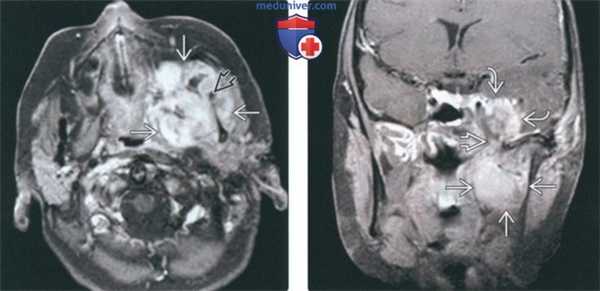

(Слева) МРТ Т1ВИ FS с КУ, аксиальная проекция. Лейомиосаркома жевательного пространства высокой степени злокачественности. Опухоль неоднородно накапливает контраст и прорастает в нижнюю челюсть. Только по данным лучевой диагностики дифференцировать различные типы сарком невозможно, за исключением случаев обнаружения матрикса остео- или хондросаркомы.

(Справа) МРТ Т1ВИ FS с КУ, коронарная проекция, тот же пациент. Новообразование, накапливающее контраст, распространяется в полость черепа через овальное отверстие. Отсюда опухоль может прорастать в пещеристый синус.

(Слева) На аксиальной МРТ (Т1 ВИ C+) в жевательном пространстве визуализируется лейомиосаркома высокой степени злокачественности, неравномерно накапливающая контраст и поражающая нижнюю челюсть. Большинство типов сарком жевательного пространства сложно дифференцировать в отсутствие костного или хондроидного матрикса.

(Справа) На корональной МРТ (Т1 ВИ С+ FS) у этого же пациента визуализируется контрастирующаяся опухоль с интракраниальным распространением через овальное отверстие а и поражением кавернозного синуса.